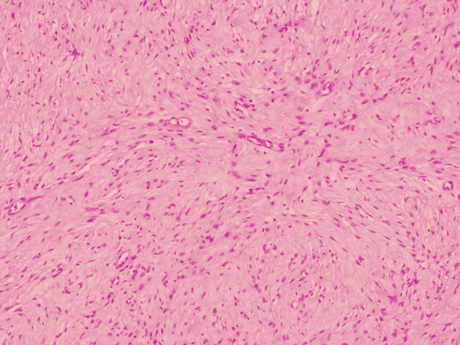

A laparotomy to remove the lesion was scheduled. An encapsulated whitish retroperitoneal tumor attached to right sciatic nerve and easily resectable by blunt maneuvers was identified intraoperatively (Figure 4). The gross specimen was a smooth nodular lesion of 5x4 cm with soft consistency. The greyish cut surface showed the presence of cystic areas. Microscopic examination revealed a well-encapsulated lesion formed by spindle cells with eosinophilic cytoplasm and elongated nuclei without cytologic atypia or pleomorphism arranged in interlacing fascicles (Figure 5) and (Figure 6). Immunohistochemical staining showed diffuse positivity of tumor cells for S-100 protein, but was negative for smooth muscle actin (SMA).

Figure 5: Spindle cell proliferation with a palisading pattern (H&E stain, x100).

The definitive diagnosis of schwannoma is based on histopathologic and immunohistochemical findings [8]. Histologically, they are characterized by alternating areas of high and low cellularity, termed Antoni A and B regions. Mitotic figures are rarely observed. Large tumors often show cystic degeneration. Immunohistochemistry is positive for S-100, neuron specific enolasa and vimentin, but negative for SMA. Schwannomas are easily distinguished from leiomyomas or malignant peripheral nerve sheath tumors (NPNSTs). Tumor cells in leiomyomas are negative for S-100, but positive for SMA. NPNSTs have poorly differentiated cells with marked nuclear atypia and frequent mitoses.